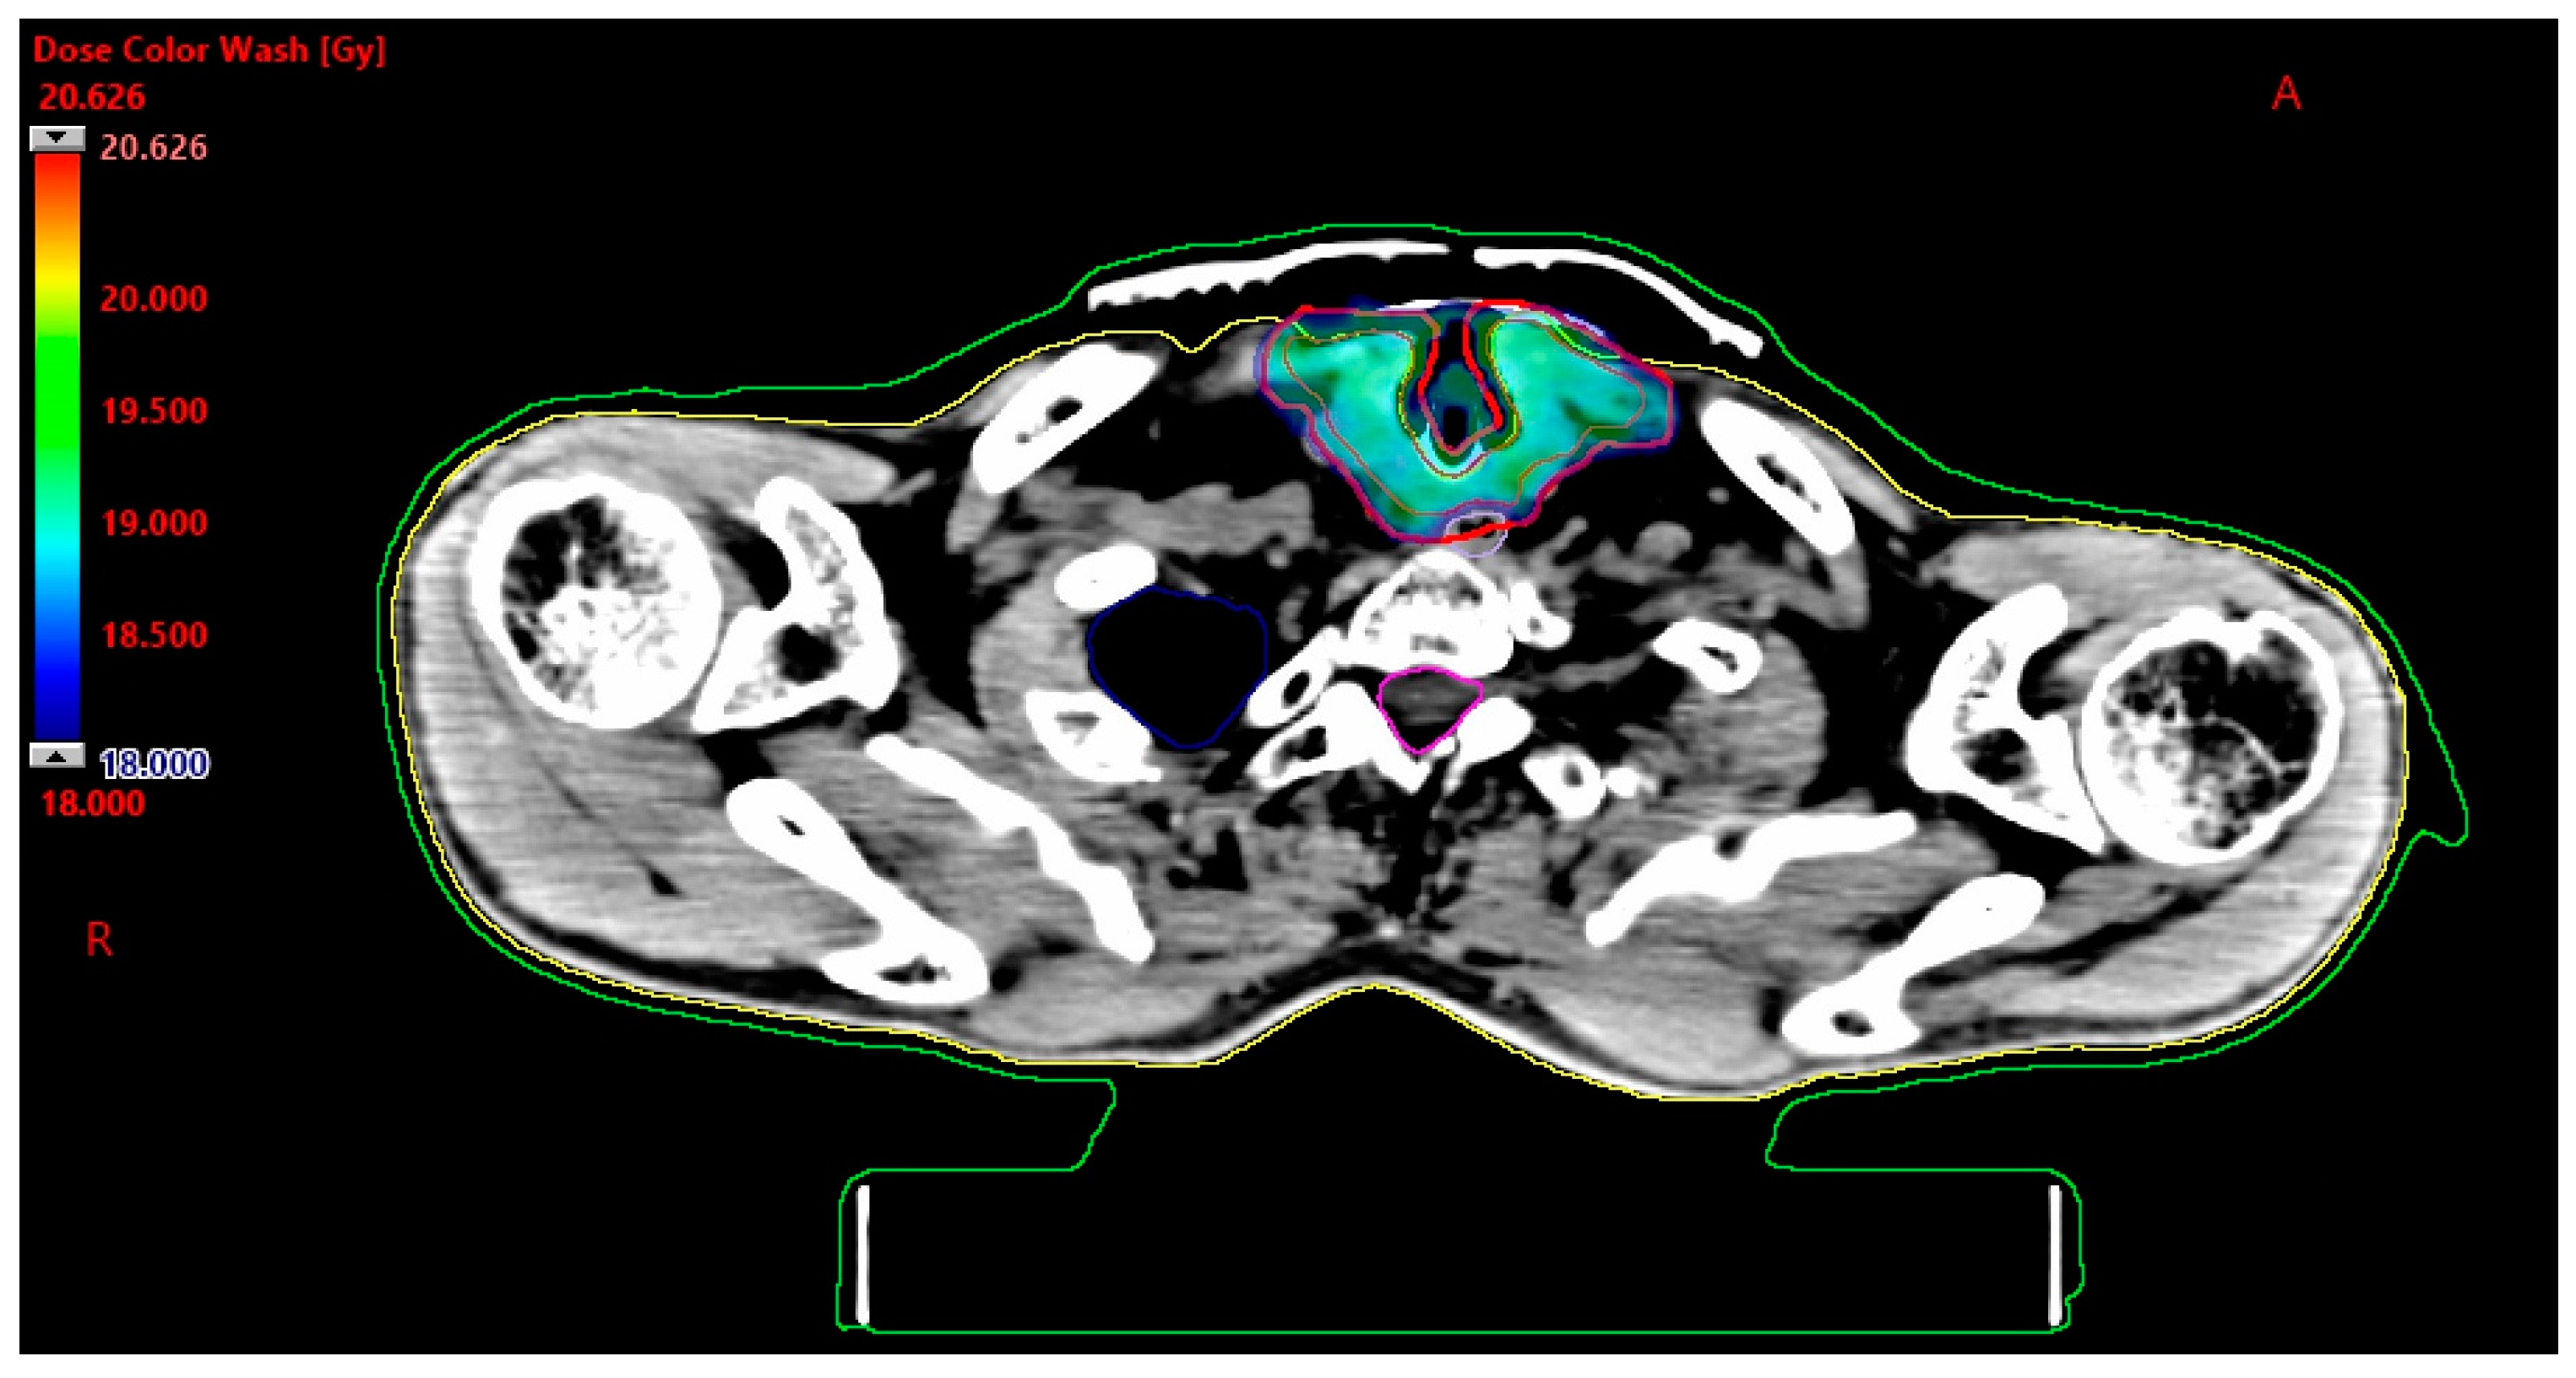

| Dmin [Gy] | Dmax [Gy] | Dmean [Gy] | |

|---|---|---|---|

| GTV | 17.0 | 20.6 | 19.0 |

| PTV | 16.2 | 20.6 | 18.9 |

| Spinal canal | 0.0 | 4.9 | 1.1 |

| Esophagus | 1.0 | 18.5 | 13.7 |

| Lung left | 0.0 | 13.3 | 0.7 |

| Lung right | 0.0 | 19.5 | 0.7 |

| Vessels left | 0.4 | 19.5 | 12.7 |

| Vessels right | 0.4 | 19.2 | 11.4 |